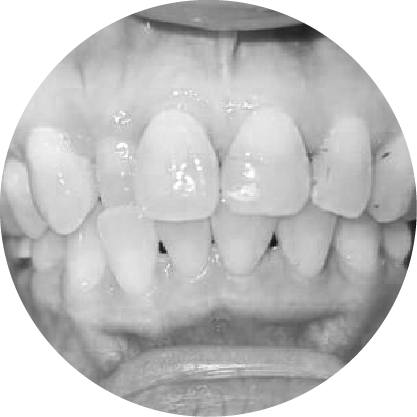

ตัวอย่างในชีวิตจริง